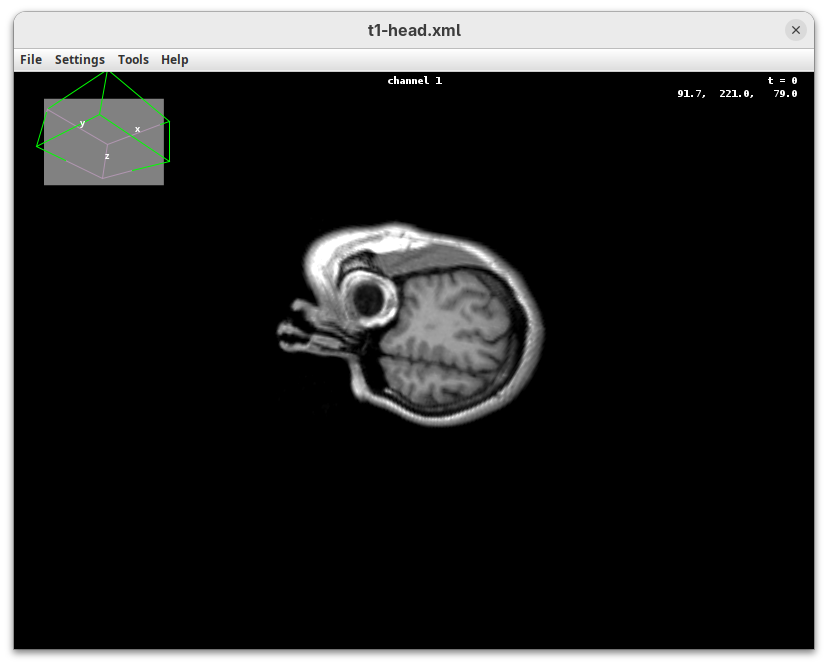

BigDataViewer (Pietzsch et al. 2015) is one of the most important tools for visualizing large, multidimensional datasets. It provides a simple and intuitive interface and shortcuts to swiftly navigate through your sample even on a regular laptop. This is possible because of the underlying file format used by BigDataViewer: the XML/HDF5 combo. Therefore, before opening the plugin, we must convert our dataset.

The BigDataViewer interface will open showing an optical section of the head sample.

Getting familiar with BigDataViewer is an essential skill for navigating large 3D datasets. It’ll also be important for the multiview registration pipeline. So, take the time to learn the basic commands and shortcuts. It is nicely intuitive. The BigDataViewer’s page on the ImageJ Docs has the official documentation and we can also go to Help > Show Help for an up-to-date overview.

Some of the movements to try:

Left-click and drag: turn the sample around the mouse pointer at any arbitrary angle.Right-click and drag: move the sample in the XY plane (of the view).Scroll: move through the Z plane (of the view). UseShift+Scrollto move fast.Ctrl+Shift+Scroll: zoom in or out.

But, most importantly, are the commands to put your sample back to its original orientation or along any of the original dimension axes:

Shift+Z: orient the sample on the XY plane.Shift+X: orient the sample on the ZY plane.Shift+Y: orient the sample on the ZX plane.

Finally, a visual tip. The default interpolation between image slices is nearest-neighbors. Press I to activate the tri-linear interpolation to obtain a much smoother (and improved) data visualization.